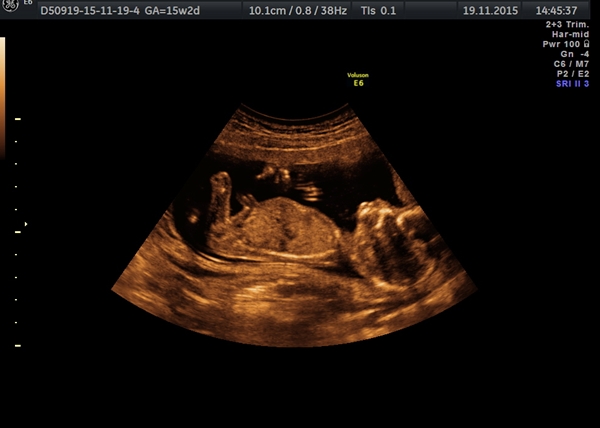

Hi :) I already know the sex of the baby but just for fun, and because there was a big doubt for the scan...

Will someone make a guess before I reveal it?

It's from 15w 2d.

Attachment 28574

Not seeing gender, any more pics?